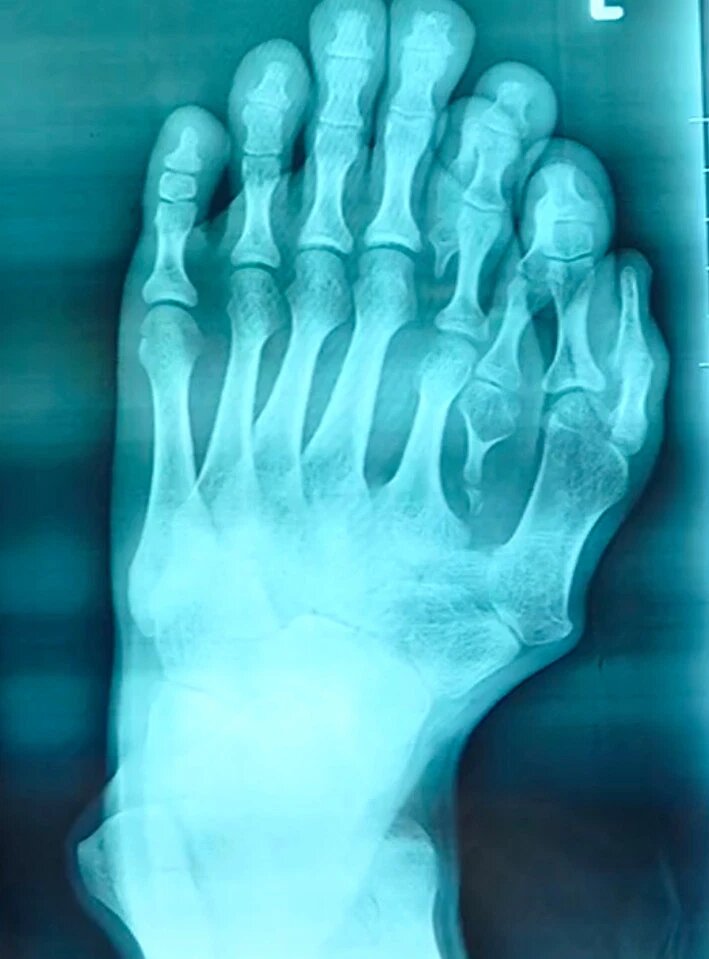

Человек, родившийся с четырнадцатью пальцами ног, десятилетиями жил с этой патологией, потому что его родители считали, что это была удача.

21-летний пациент, которого зовут просто «Аджун», говорит, что четыре дополнительных пальца на левой ноге вызывали у него столько стыда, что уже в 10 лет он перестал носить открытые сандалии.

Его доктор Ву Сян сказал: «Очень редки случаи, когда такая серьезная деформация наблюдается без лечения у 21-летнего пациента.»

«Его естественный палец ноги находится снаружи, поэтому мы решили перенести его внутрь в самое идеальное положение, сместив пятую часть пальца и создав новый большой палец ноги.»

Такое странное уродство встречается крайне редко — но родители мальчика думали, что это большая удача. Фото: AsiaWire